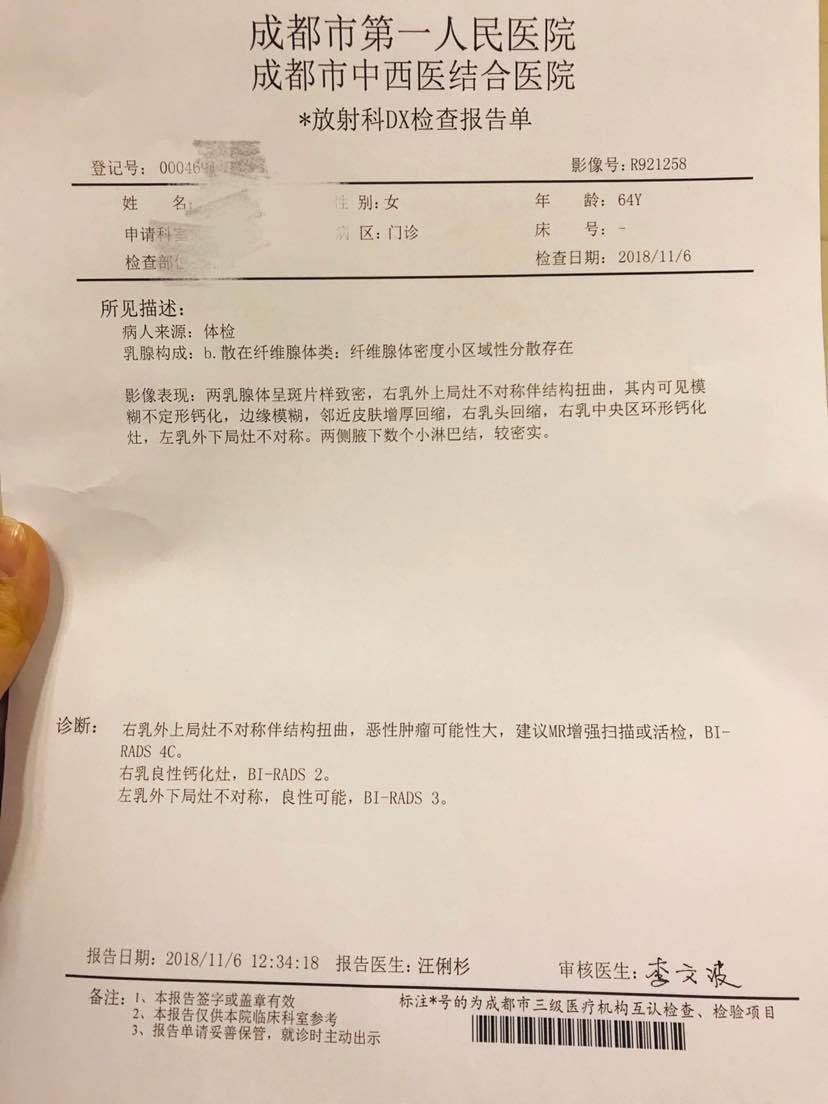

这是第一家医院做的检查

第二家的。有懂的朋友吗?我们也做了最坏的打算,会和我妈妈一起努力的!